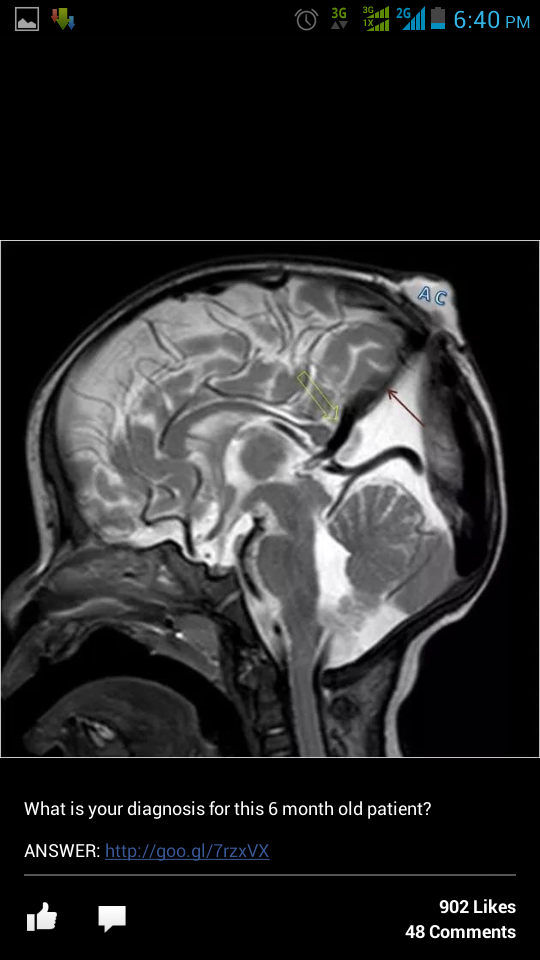

X rays collection